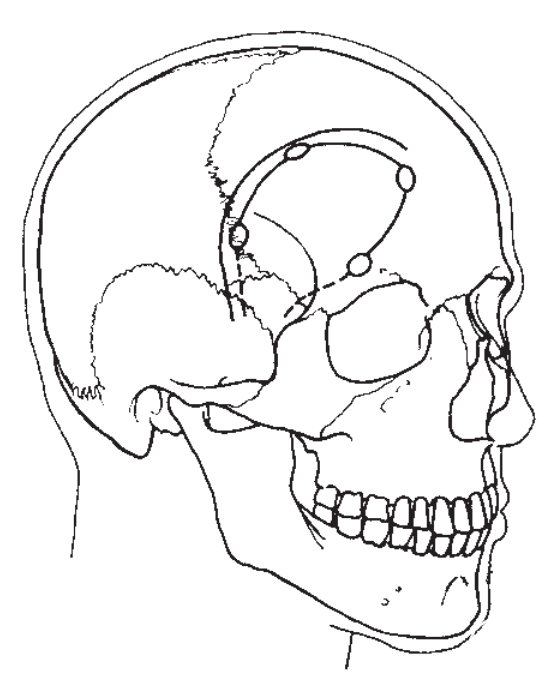

额外侧入路更靠近额部,骨窗2/3位于颞上线以上,1/3位于颞上线以下(Brock M, 1978年)。

额外侧入路的皮肤切口和骨瓣。

额外侧入路的艺术家视图。可见:额外侧入路是从前颅底外侧进入鞍区,并非直接沿着蝶骨嵴、外侧裂进入。